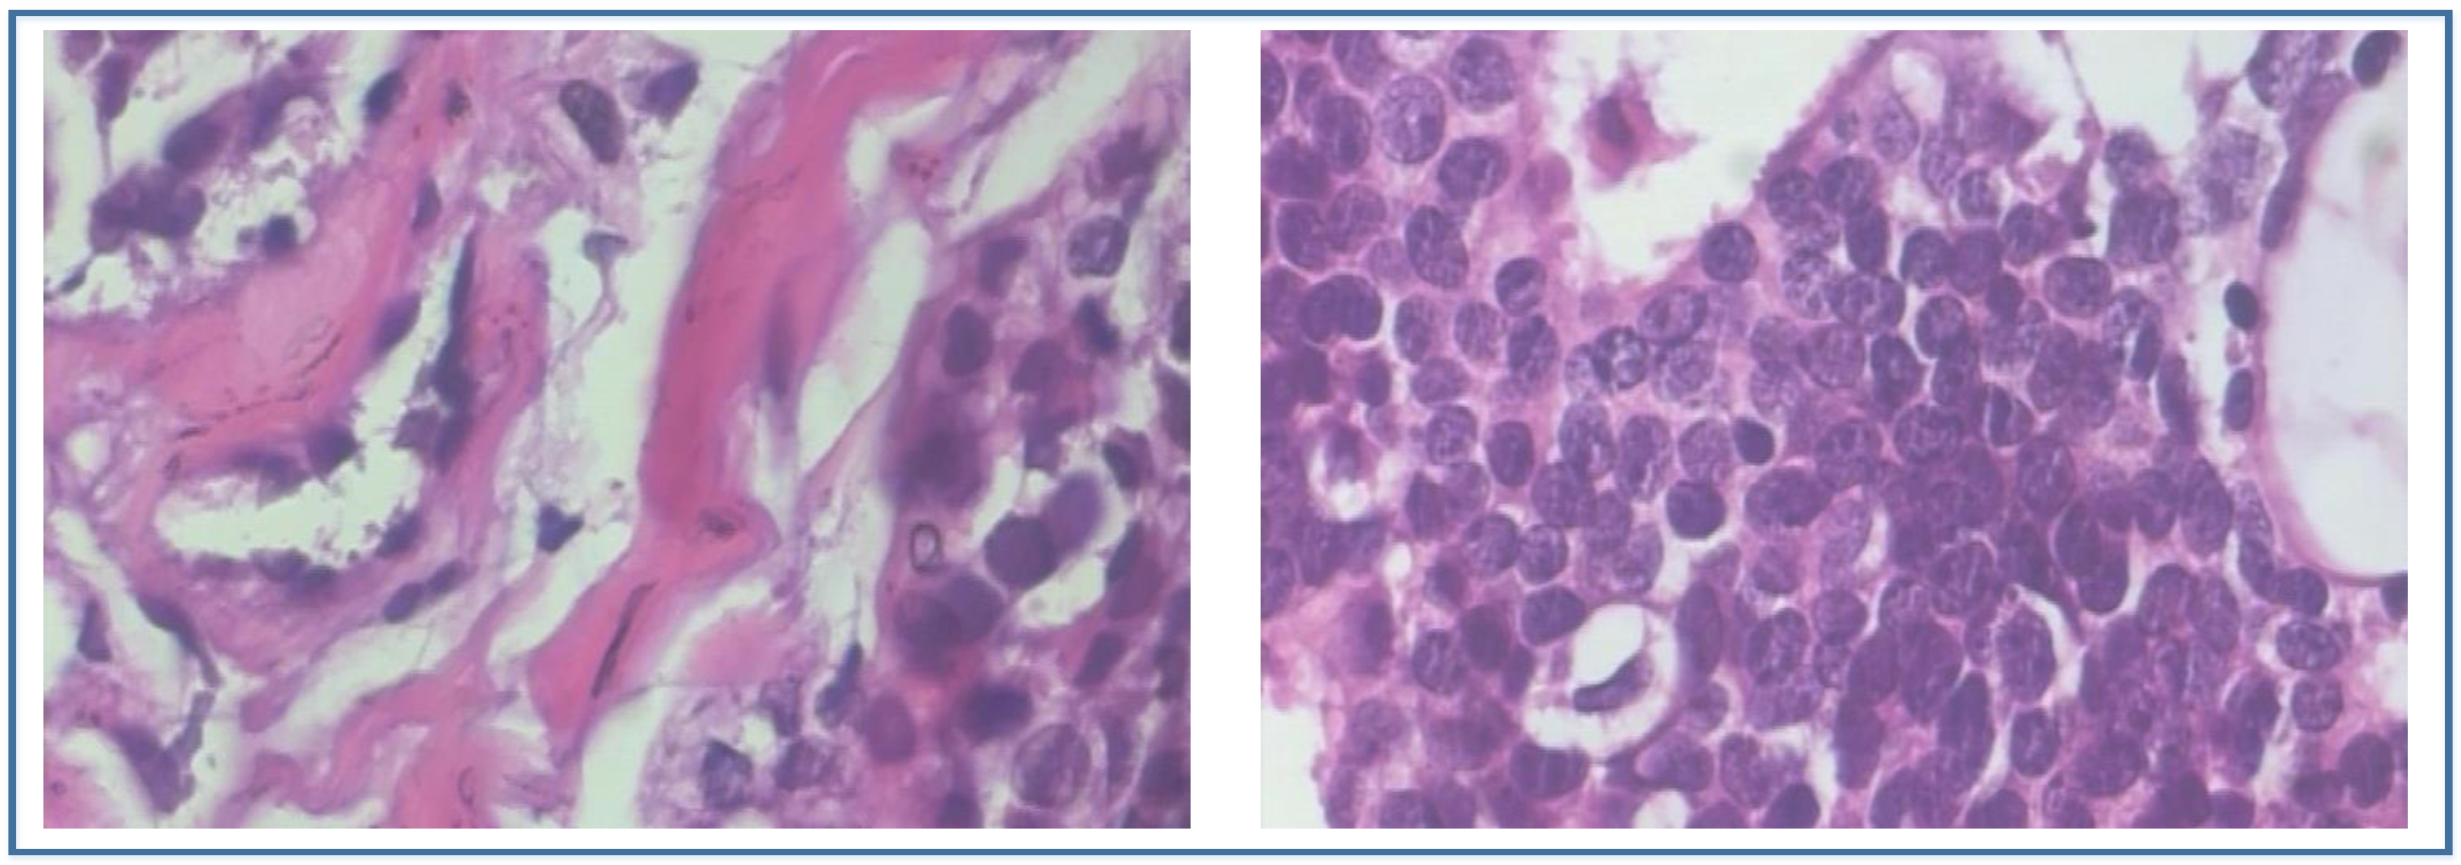

- Spanhol, F.A.; Oliveira, L.S.; Petitjean, C.; Heutte, L. A dataset for breast cancer histopathological image classification. IEEE Trans. Biomed. Eng. 2016, 63, 1455–1462. [Google Scholar] [CrossRef] [PubMed]